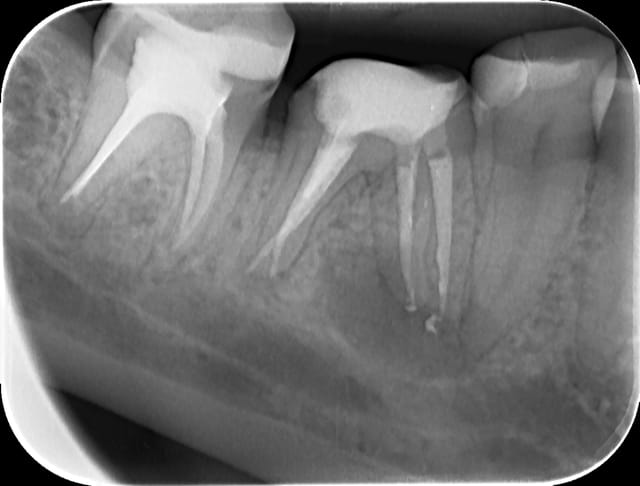

46 - fig 1,2 situation initiale

Fase du traitement: seule visite 2h

- percussion - positive

- teste du vitalité - négative

NaOCl 5% - l'irrigation et l'activation par ultrasons

chaud condensation de gutta-percha

build-up

Apres obturation - fig.3,4